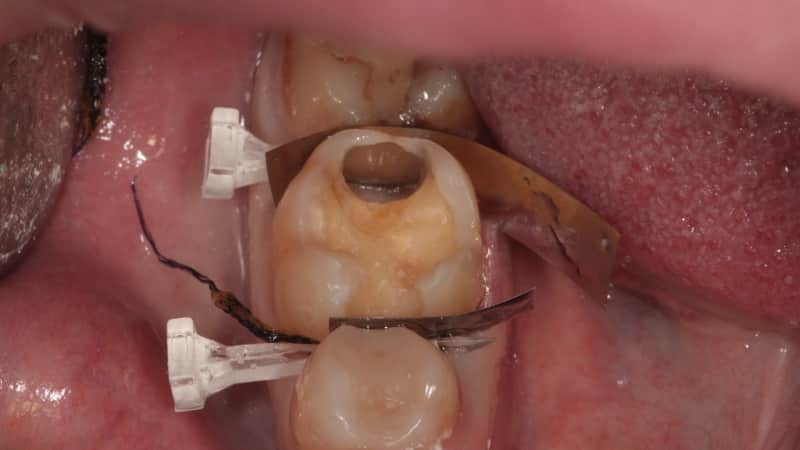

Визуальная диагностика является стандартной практикой в каждой стоматологической клинике и включает использование специального зонда и стоматологического зеркала. При зондировании важными параметрами являются глубина поражения зуба, степень разрушения, структура и твердость затронутых тканей, а также состояние дентина. Визуальный осмотр при данном заболевании может быть довольно неприятным, так как полость может достигать области пульпы (нерва), что вызывает болезненные ощущения или даже кровоточивость.

При визуальном осмотре поврежденной области можно заметить глубокую полость, покрытую некротическими черными и темными тканями, остатками разложения и следами микробной активности. Часто на таких зубах образуется темный камень и плотный желтый налет.